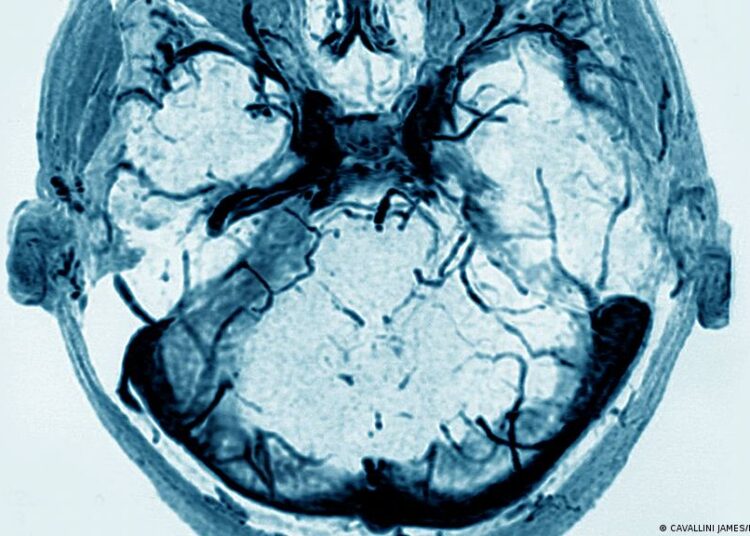

Dicho en sencillo, las plaquetas actúan en la sangre para impedir las hemorragias. Cuando sobreabundan, forman coágulos o trombos. En condiciones normales, las plaquetas se activan cuando se produce una herida, para hacer que ésta cicatrice. Sin embargo, en algunos pacientes, la vacuna de AstraZeneca desata esta reacción de forma descontrolada, haciendo que se formen coágulos de sangre en el cerebro.